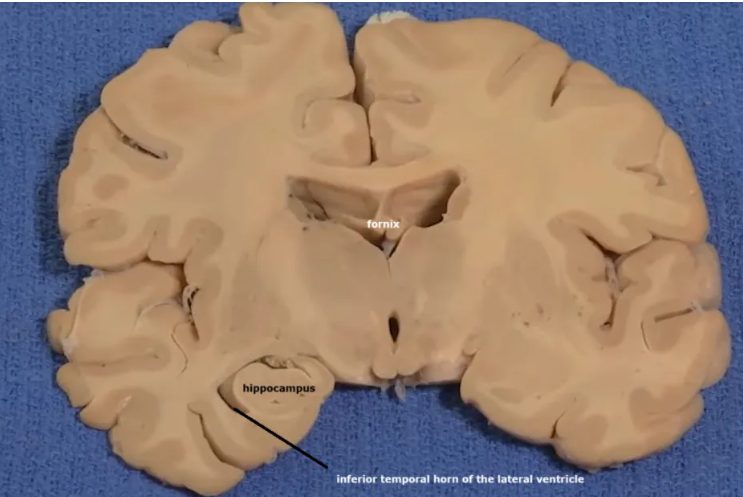

Thalamus (pink) and hypothalamus (yellow): their medial surfaces border the third ventricle (blue).

Overlaying the green cingulate and parahippocampal gyri with the purple hippocampus highlights the limbic lobe. Yellow = fornix. Brownish pink = hypothalamus

The purple hippocampus is visualized tracing the ventricular system (turquoise).